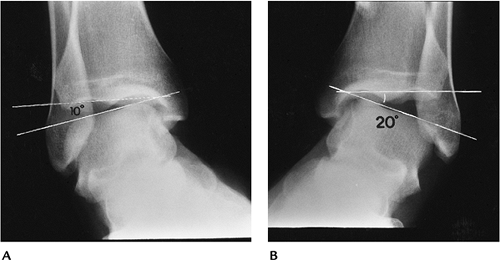

FIGURE 6-40 Stress views. Normal ankle (A) and injured (B)

ankle shows that the joint laterally on the injured side is 10 degrees greater than the normal side because of tears in the calcaneofibular and anterior talofibular ligaments. |